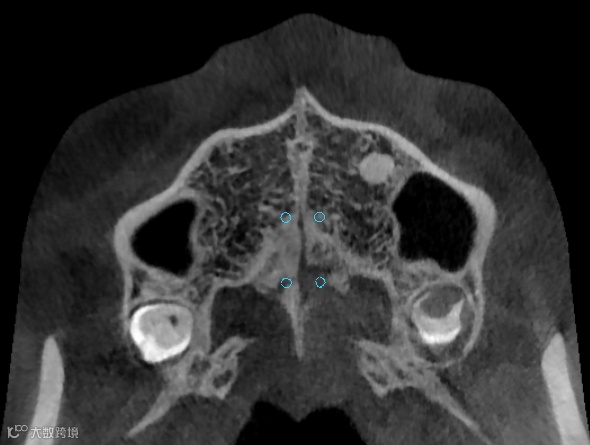

CBCT精准定位

种植导板设计及打印

我们能为您提供MSE的数字化精准定位

提供个性化的MSE支抗钉植入导板

以确保MSE的精准制作